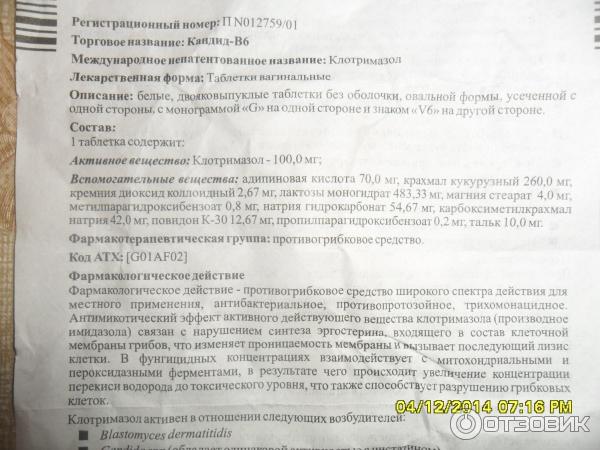

Механизмы действия антимикотиков: схемы и изображения